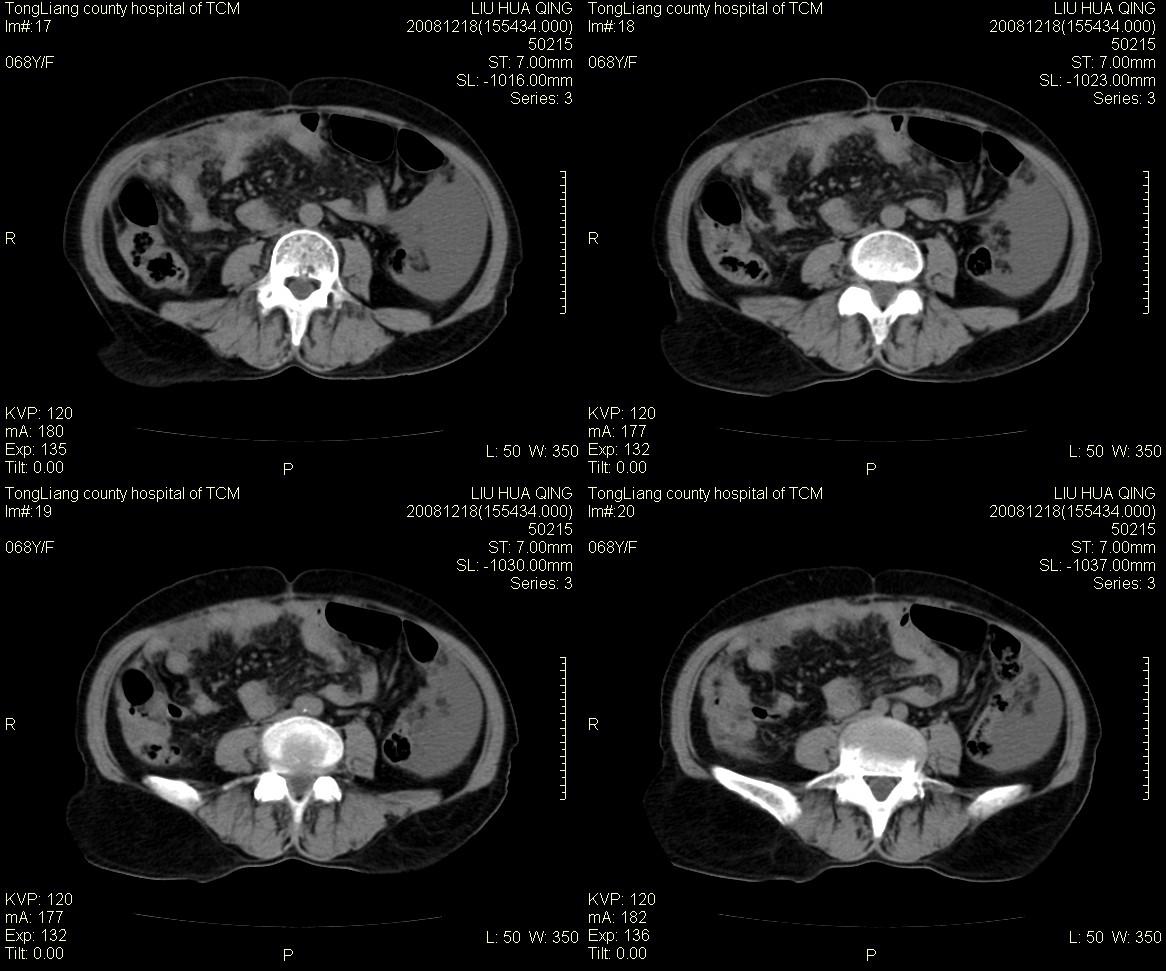

女,68y,下腹疼3月,一月半前院外ct示上腹未见异常。近1月来,症状加重。4天前入院,b超示胸腹水。今日呕吐频繁。  生化检查:  结核抗体阴性,血沉18mm/h, 癌胚抗原阴性,胸水细胞学检查见多数淋巴细胞。 白细胞总数5.4x10^12/l,血红蛋白104g/l.

患者右中腹部肠管聚集,内密度不均,可见片絮状及结节样增密影,小肠壁增厚,与之相邻处有软组织影。

腹腔积液可以肯定,原因?右侧下腹肠壁增厚,周围脂肪密度增高,粘连坏死?---梗阻坏死(不像)还是血栓坏死,占位?期待结果。

1)右侧腹腔前部见类似“网膜饼”样改变,考虑网膜转移瘤。2)腹水。

腹膜污染[大网膜增厚可见污垢征及小班结与饼片影,肠系膜增厚],大量腹水。考虑癌性腹膜炎,建议查腹水。结核待排.注意上腹部及胃肠道检查